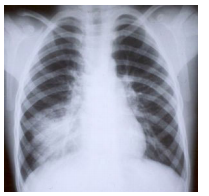

Um homem de 30 anos, anteriormente hígido, apresenta

febre, tosse e dor ventilatório-dependente no hemitórax direito há 1 dia. Refere ter tomado cefalexina por 1 semana

há cerca de 45 dias devido a ferimento por trauma no pé.

A radiografia de tórax mostra:

O médico decide por tratamento ambulatorial. Dentre as

opções terapêuticas abaixo, a PIOR opção é